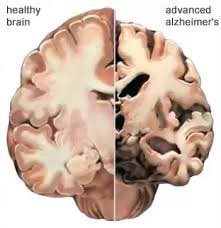

ضمور المخ هو فقدان خلايا الدماغ التي تسمى العصبونات،فيؤدي إلى حدوث خلل في الاتصالات التي تساعد الخلايا على التواصل

2️⃣كما ويسبب ضمور المخ حدوث العديد من الأمراض المختلفة التي تضر الدماغ،بما في ذلك السكتةالدماغية ومرض الزهايمر.

* مرض الزهايمر:الخرف الأمامي الصدغي أيضاً

*لايوجد علاج حقيقي لضمور الدماغ الناتج عن مرض الزهايمر،أو مرض هنتنغتون